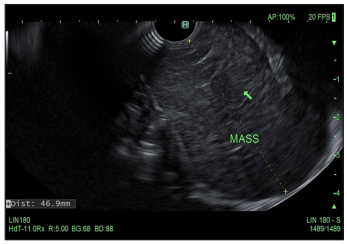

A 44-year-old male with a history of HTN presented with progressive dysphagia to solid food over the last 6 months. Physical examination, vital signs and initial basic laboratory work up were largely unremarkable. CT scan of the chest with contrast revealed a 4cm x 4cm posterior mediastinal mass at C2-C4 levels behind the trachea, with resultant distortion of the esophagus (Figure 1). Endoscopic ultrasonography (EUS) revealed extrinsic compression in the upper third of the esophagus by a large hypoechoic lesion (Figure 2). Fine needle aspiration (FNA) was performed with cytology revealing smooth muscle tumor with nuclear atypia raising concern for leiomyoma (Figure 3). As a result, patient was referred to our Cardiothoracic Surgery Team for surgical excision (Figure 4).

Figure 2: A round intramural (subepithelial) lesion was found in the upper third of the esophagus. The lesion was hypoechoic and heterogenous. The endosonographic borders were well-defined.